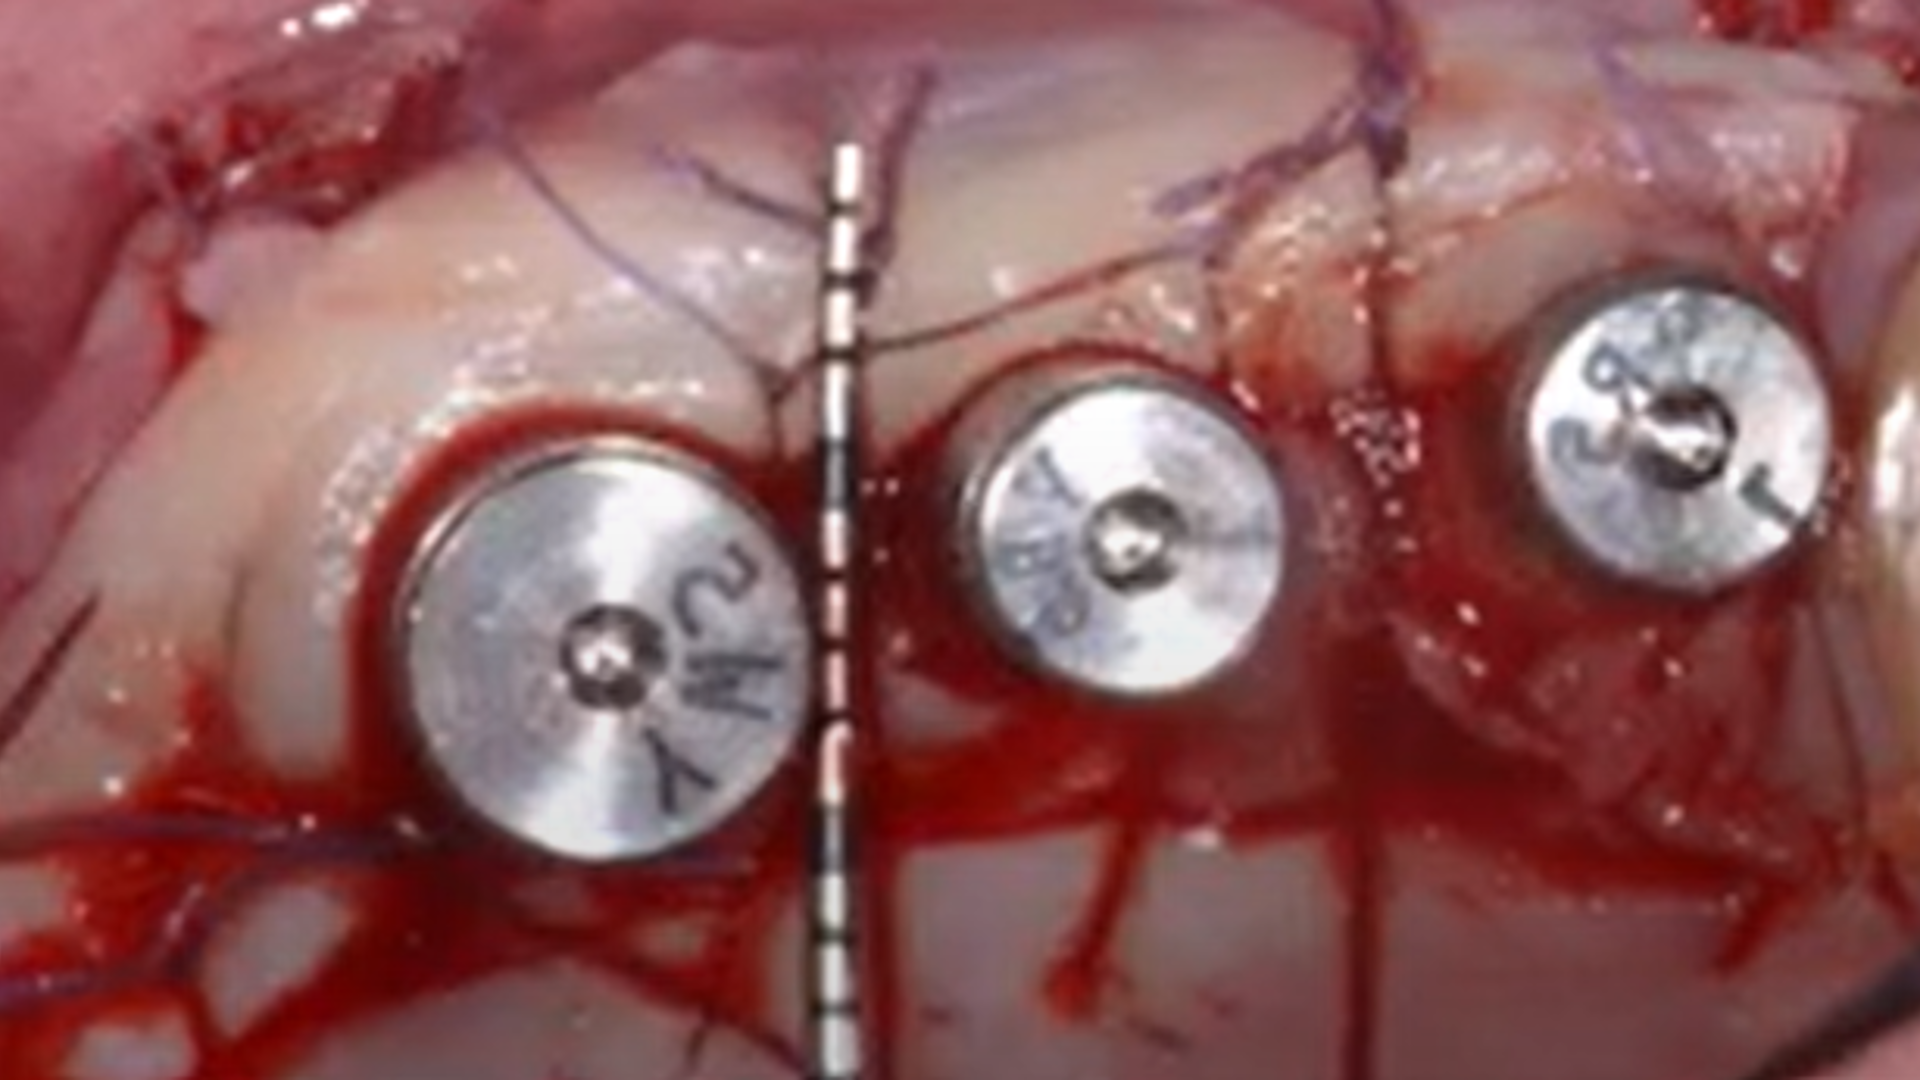

Osseodensification technique

Clinical video: short implants + Versah crestal sinus lift

Clinical video: Crestal sinus lift and multiple implant placement